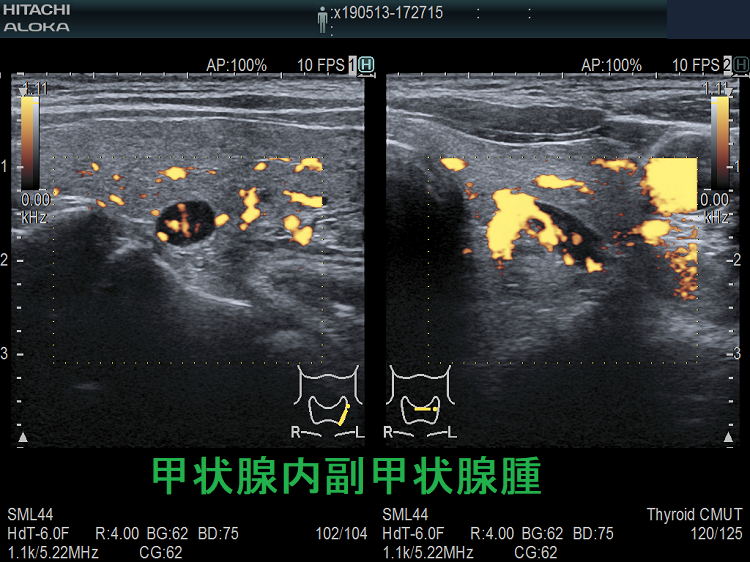

(➸)原因となる副甲状腺腺腫、副甲状腺癌、副甲状腺過形成をデジタルハイビジョン超音波診断装置で診断。エコーでは、甲状腺とのインピーダンスの違いにより、甲状腺-副甲状腺境界部に線状高エコーが生じます(右図の↓)。内部は中心血流を認め、リンパ節でないのが分かります。

甲状腺内副甲状腺腫は、原発性副甲状腺機能亢進症の1.4 ~ 2.1%を占めます[Surgery. 2009 Dec;146(6):1144-55.]。

甲状腺内副甲状腺腫は、超音波(エコー)検査で甲状腺腫瘍と形態的に鑑別できない場合があります(実際は下の写真のように診断できていますが・・)。特徴的な超音波(エコー)所見は、腹側の高エコーで感度86%、特異度100%です[Surgery. 2012 Dec;152(6):1193-200.]。さらに、99m-Tc MIBIシンチグラフィーで取り込み(集積)があれば甲状腺内副甲状腺腫と診断できます。

99m-Tc MIBIを取り込まない甲状腺内副甲状腺腫もあるため、穿刺細胞診を行い、針先洗浄液でインタクトPTHを測定(FNA-PTH)。甲状腺内副甲状腺腫は、甲状腺が周囲にあるため、針に沿った副甲状腺細胞のばらまき(播種)・出血の危険が少なくなります。